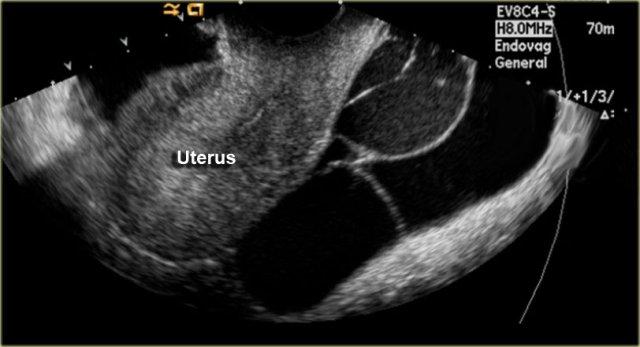

Nang Vùi Phúc Mạc

Còn được gọi là Nang vùi phúc mạc đa thùy hoặc U trung biểu mô nang lành tính.

Đây là khối u phúc mạc nguyên phát lành tính hiếm gặp, không có liên quan đến

Các loại nang mạc treo khác như nang nhân đôi ruột, nang ruột, giả nang không do tụy và nang trung biểu mô rất hiếm gặp và không có đặc điểm hình ảnh đặc trưng. - Nang vùi phúc mạc (Peritoneal inclusion cyst)

là một khối u phúc mạc nguyên phát lành tính, ít gặp hơn.

Tổn thương này còn được gọi là u trung biểu mô đa nang lành tính (benign multicystic mesothelioma).

Tên gọi này dễ gây nhầm lẫn vì không có mối liên quan với u trung biểu mô ác tính.

Tổn thương thường gặp ở phụ nữ có tiền sử phẫu thuật phụ khoa hoặc nhiễm trùng vùng chậu.